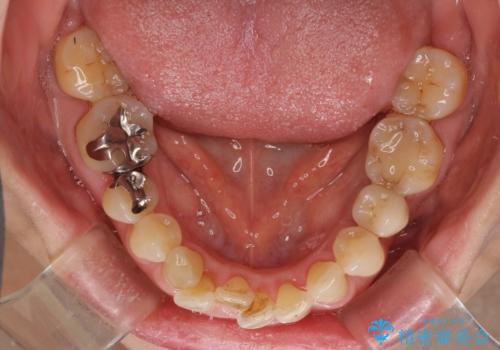

口元の出っ張りとデコボコを改善したい

- 近医にてインプラント治療を行った後に矯正治療を希望され、来院された患者様です。

口元の突出感とデコボコが気になっているとのことでしたが、インプラントが既に3本埋入されていたため、抜歯矯正による口元を引っ込めることができない状況でした。

近医での歯周病治療の影響でブラックトライアングルが発現していたため、IPR(歯と歯の間を削る)で隙間を改善しつつ、インプラントを固定源に歯列全体を後方へ移動させることとしました。